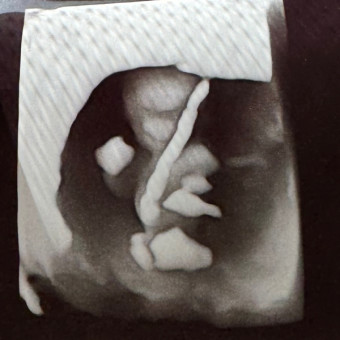

Zamiree & Noah’s Baby Registry

Zamiree Britt & Noah Dobson

Oklahoma City, OK

November 3, 2024